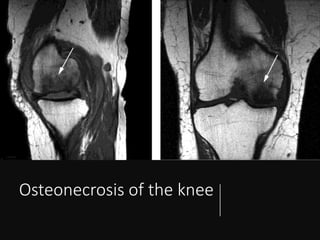

• X RAY

- slight flattening of medial femoral condyle on both AP & lateral views

- MRI

- evidence of well localized osteonecrosis in lateral condyle & extensive

involvement of the medial condyle

- T1 images show decreased signal